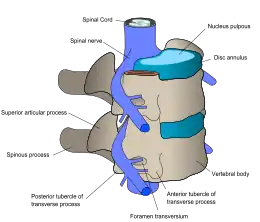

The lumbar (or lower back) region is the area between the lower ribs and gluteal fold which includes five lumbar vertebrae (L1–L5) and the sacrum. In between these vertebrae are fibrocartilaginous discs, which act as cushions, preventing the vertebrae from rubbing together while at the same time protecting the spinal cord. Nerves come from and go to the spinal cord through specific openings between the vertebrae, receiving sensory input and sending messages to muscles. Stability of the spine is provided by the ligaments and muscles of the back and abdomen. Small joints called facet joints limit and direct the motion of the spine.[34]

An intervertebral disc has a gelatinous core surrounded by a fibrous ring.[36] When in its normal, uninjured state, most of the disc is not served by either the circulatory or nervous systems – blood and nerves only run to the outside of the disc.[36] Specialized cells that can survive without direct blood supply are in the inside of the disc.[36] Over time, the discs lose flexibility and the ability to absorb physical forces.[27] This decreased ability to handle physical forces increases stresses on other parts of the spine, causing the ligaments of the spine to thicken and bony growths to develop on the vertebrae.[27] As a result, there is less space through which the spinal cord and nerve roots may pass.[27] When a disc degenerates as a result of injury or disease, the makeup of a disc changes: blood vessels and nerves may grow into its interior and/or herniated disc material can push directly on a nerve root.[36] Any of these changes may result in back pain.[36]